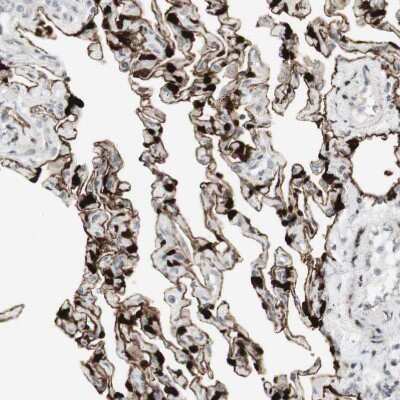

Immunohistochemistry-Paraffin: SARG Antibody [NBP1-81956] - Staining of human lung shows strong membranous positivity in pneumocytes.